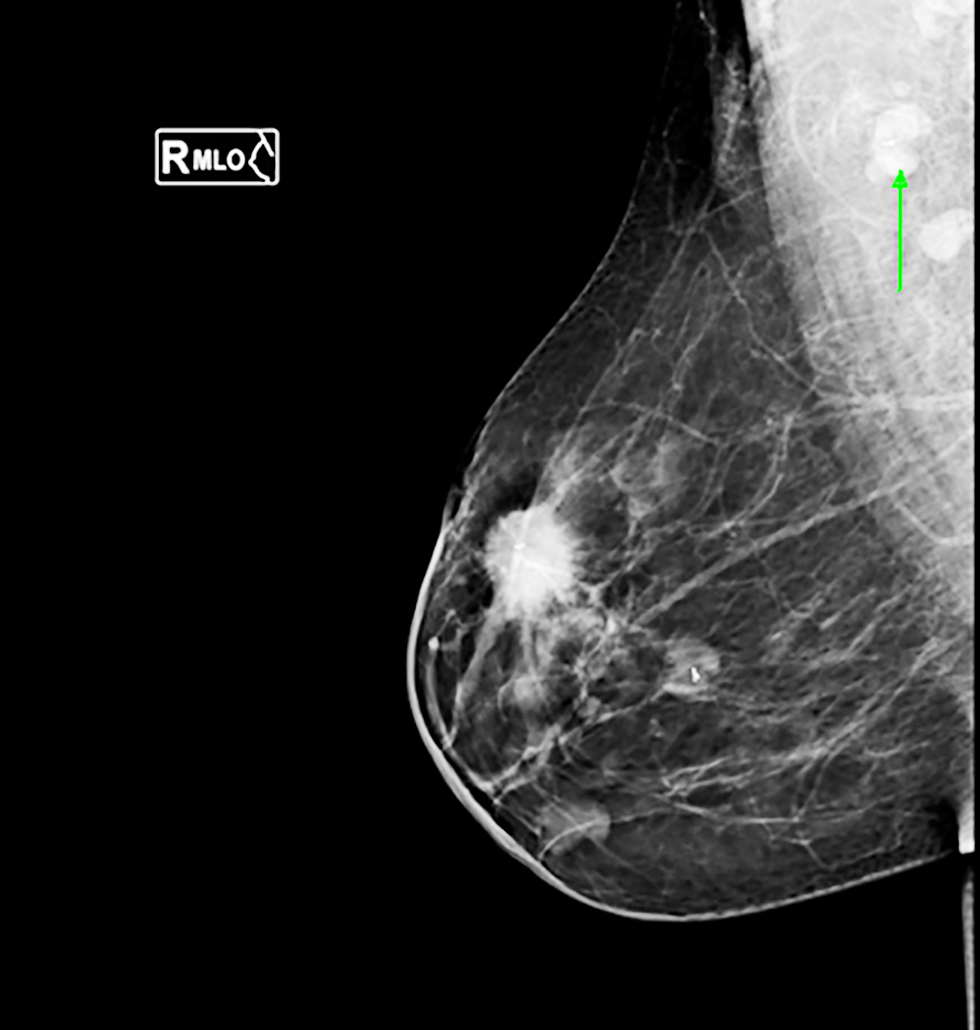

Figure 2 - Mammogram imaging showing ultrasound-guided clip placement of a pathological right axillary lymph node in a triple-negative breast cancer case

For cN1 patients, suspicious nodes underwent US-guided clip placement pre-NAC using titanium clips. Post-NAC, patients with clipped nodes underwent wire localization before surgery under US guidance (15).

The lymph node was submitted for paraffin section assessment to reassess the frozen section results, with management modified accordingly. An example of retrieved clipped lymph node is shown in fig. 1, while clip placement procedures are illustrated in figs. 2, 3, and 4.